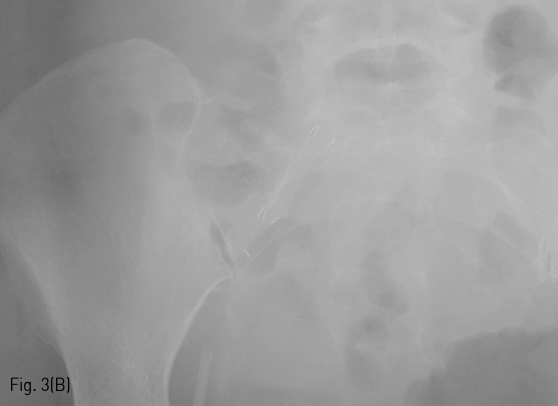

내원 당일 시행한 CT상 췌장 이식 편은 조영증강이 되지 않으며 안에 necrosis로 생각되는 air bubble이 있다 (Fig. 2A). 또한 이와 인접하여 이식편과 문합되어 있는 proximal right external iliac artery에 가성 동맥류가 있다(Fig. 2B).

Fig 2A

(A, B) On contrast-enhanced CT scan after the development of symptom, there was necrosis (arrow) of transplanted pancreas graft with pseudoaneurysm formation in adjacent proximal right external iliac artery.